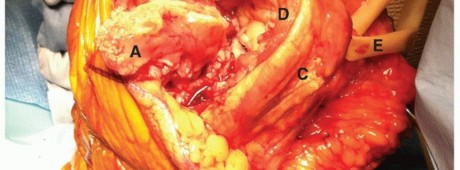

FIG 1 • A. Deltopectoral incision. B. Axillary incision beginning inferior to the tip of the coracoid and progressing toward the anterior axillary fold. C. In this dissection, the subscapularis tendon is being tagged at the superior border of the rotator interval.

The superior border of the subscapularis muscle blends in with the fibers of the supraspinatus muscle in the rotator interval (FIG 1C).